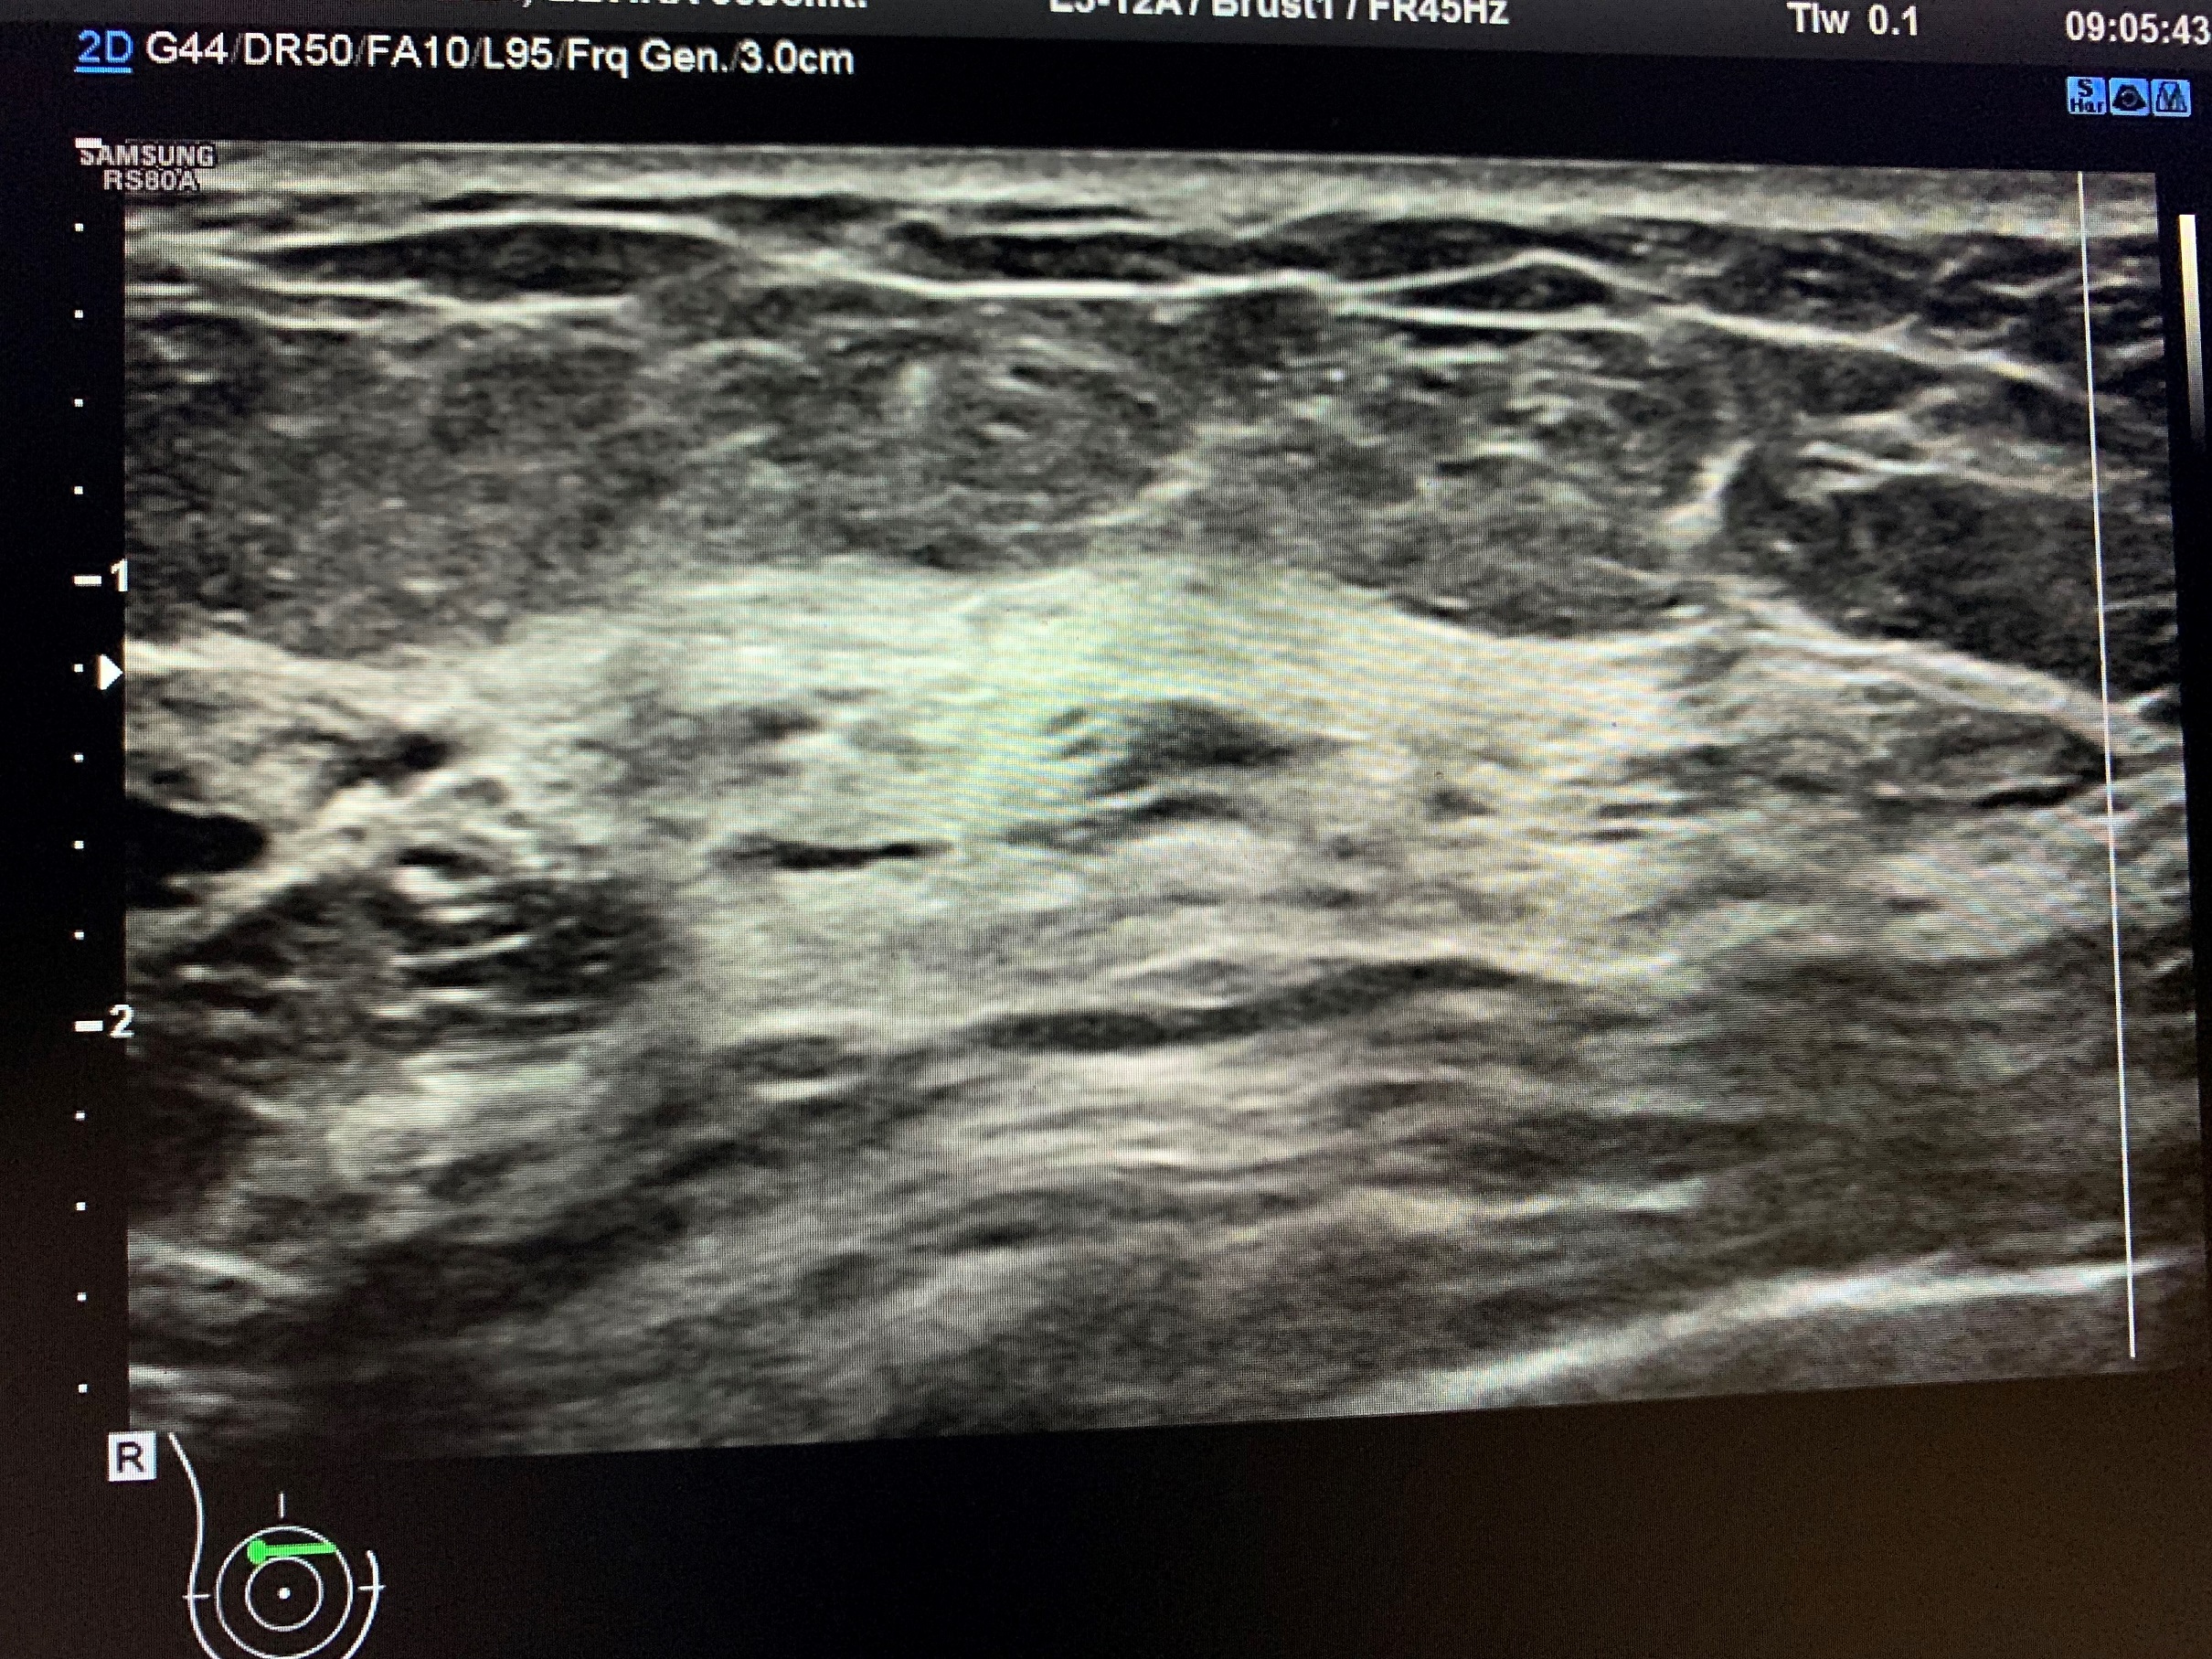

Pamje nga Ultratingulli i gjirit